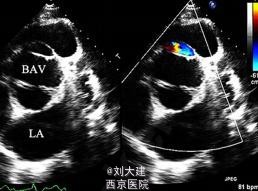

体格检查在左侧第三肋间闻及 3/6 级的「拉锯样」杂音。胸片检查发现心影增大,心电图显示完全左束支传导阻滞伴频发室早。经胸壁心脏超声显示左心室极度扩大,左心室舒张末期容积为 472 ml,射血分数(EF)为 20%。

心脏超声和多层 CT 血管造影发现一隧道样结构,伴收缩期顺流和舒张期逆流,该结构起源于主动脉根部,刚好位于扩张的主动脉窦水平之上,缠绕左下进入左心室。最终诊断为 II 型 ALVT(以隧道结构的心脏外主动脉壁动脉瘤伴或不伴瓣膜变形为特征),术中探查后明确诊断,手术关闭隧道后患者表现良好。